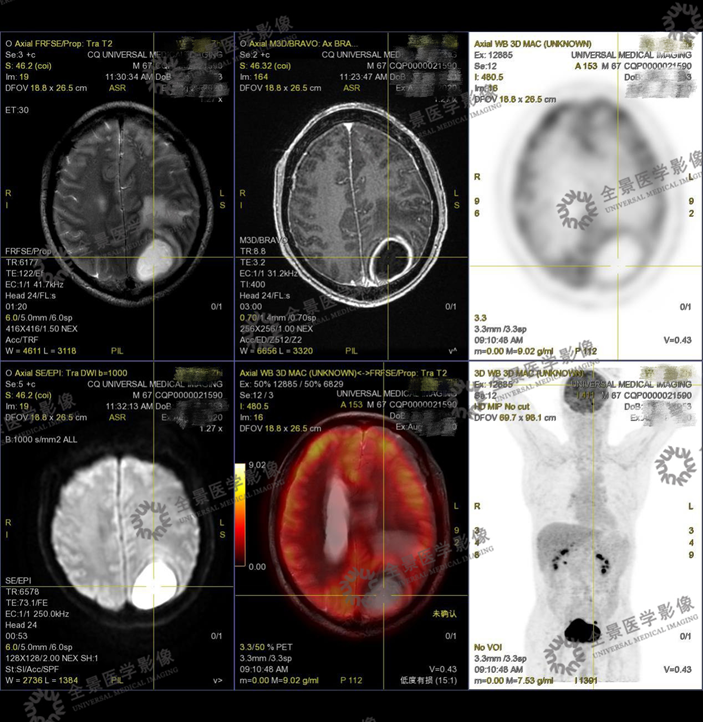

案例2 :中老年男性,总感觉头晕,外院做头颅增强CT,提示左侧顶叶多发环形强化结节,怀疑脑转移瘤。为进一步明确诊断,行PET/CT-MR异机融合检查。

表现:左侧顶枕叶脑脓肿,邻近脑实质、左侧侧脑室明显受压,右侧脑积水。